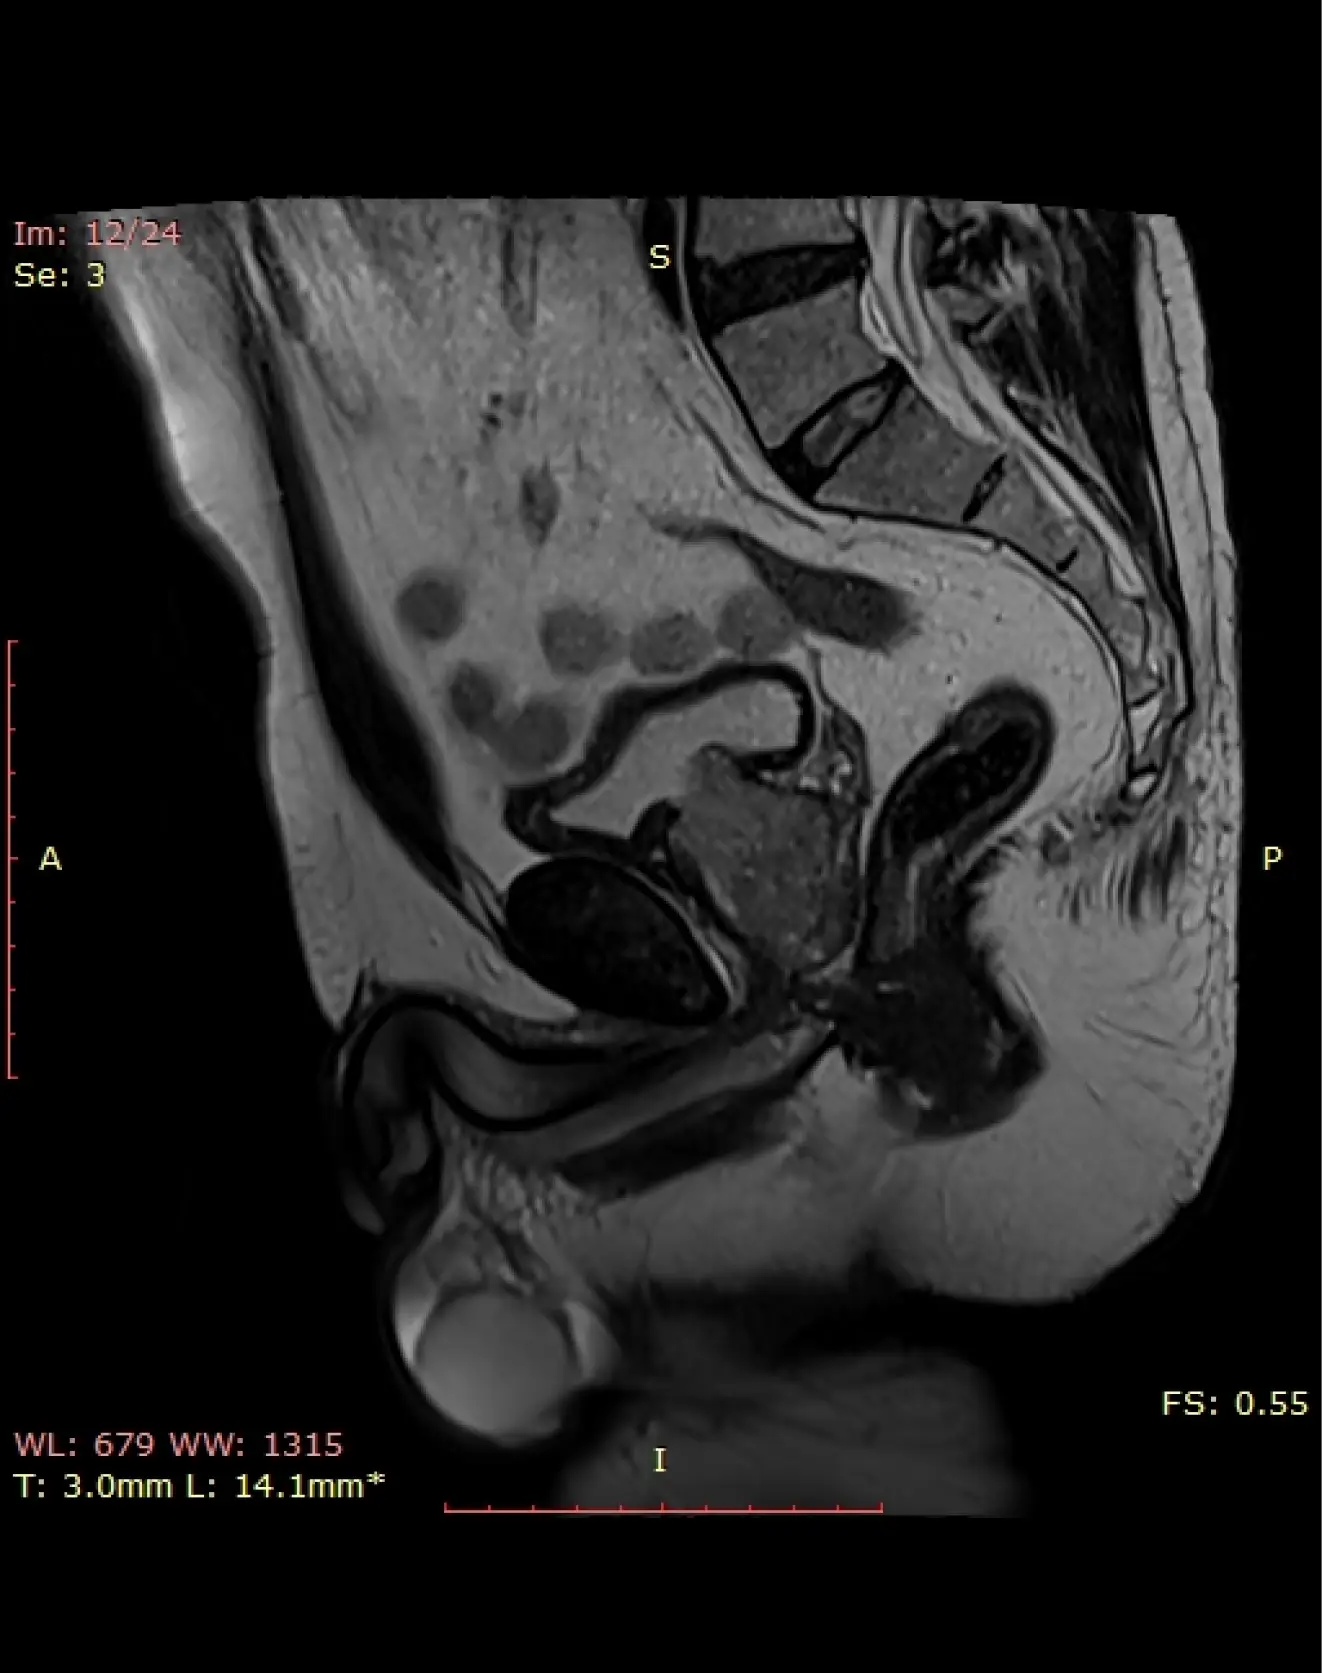

МРТ малого таза у мужчин

Визуализация предстательной железы, семенных пузырьков, мочевого пузыря, лимфоузлов, прямой кишки.